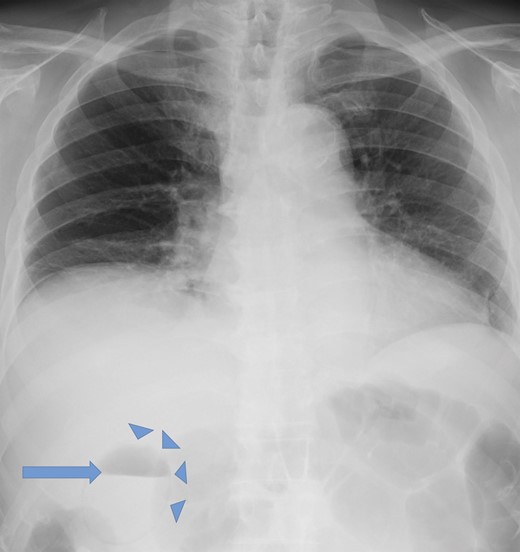

A 78-year-old male was admitted to our hospital for an investigation of vertigo. He had past medical history of diabetes mellitus, hypertension and dyslipidemia. After admission, he developed fever and abdominal distention. A chest X-ray in the up-right position and abdominal computed tomography (CT) were performed. The chest X-ray showed the presence of gas within the gallbladder and in its wall (Fig. 1). The CT scan revealed emphysematous changes in the gallbladder wall and air within the gallbladder (Fig. 2A and B). Therefore, a diagnosis of EC was made. The patient was referred to the Department of Surgery and emergent surgery was performed.

Up-right chest X-ray demonstrating air in the gallbladder (arrow) and in its wall (arrowheads).

The symptoms of EC are almost the same as those of acute cholecystitis, including right upper quadrant pain, nausea, vomiting and low-grade fever [2, 4]. A prompt diagnosis of EC is essential and plain abdominal X-rays or ultrasound can be diagnostically useful with a sensitivity of up to 95% [2]. However, contrast-enhanced abdominal CT scans may offer more information [1]. In our patient, a chest X-ray in the up-right position detected air in the gallbladder wall and an abdominal CT revealed typical presentation of EC.